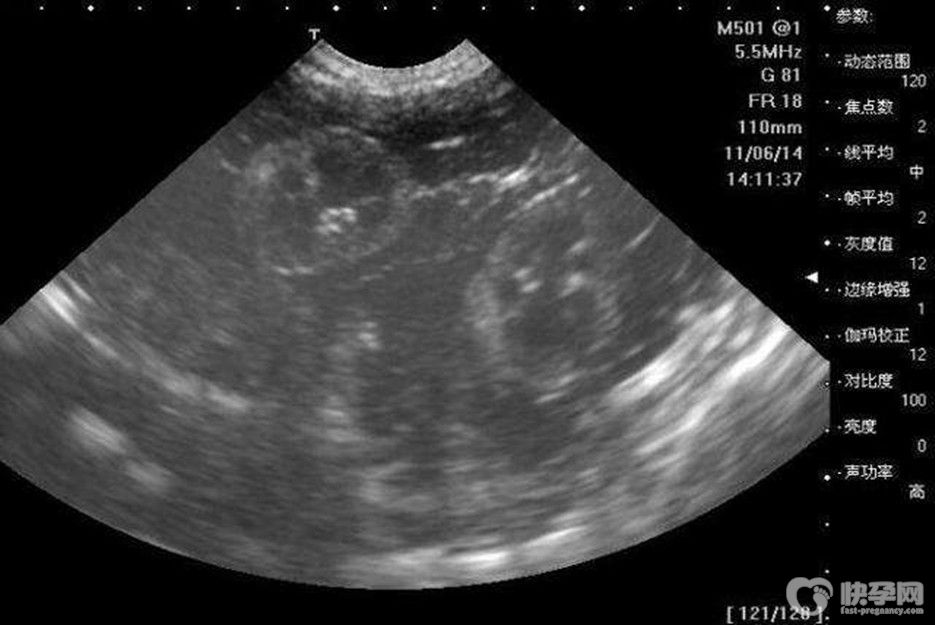

根据B超数量看男女:

1、60天的BC数据: 孕囊大小是3.6*1.6MM生下的是帅哥

2、5W+6D。 孕囊:25mm*11mm 男孩

3、7W+ 1D的BC数据:胎囊2.9*1.9生的是男孩

4、数据:胚囊:23x17x16 生下的是小女

5、46天BC数据:孕囊:20*17*17女孩

6、7w+ 1D的BC结果:32*20mm妊娠襄女孩

7、9W+ 4D的BC数据:言内见46.6*30.2mm孕囊双胞胎都是女孩

8、7周多的B超数据宫内见3.8*2.3CM妊娠囊生的是男宝宝

9、孕囊长为44*20mm生的是男宝宝

10、 8周时是1.6x1.7生下的是千金

11、8周的时候是41*28MM生下的也是女宝宝

12、8周多是的BC,胎囊是19MM*10MM后来BC照出来也是男宝宝

13、胎囊:35mmX34mmX28mm 可爱的女宝宝

14、孕囊大小:(长)1 8MM X(宽)1 6MM X (厚)8MM今年四月份生的粉可爱女宝宝

15、62天:内见孕囊2.6*1.8生的是可爱的男宝宝

16、50天,孕囊35MM*27MM生的是女宝宝

17、孕囊33*18 现B超是男宝宝.

18、 3.3*2.0cm可爱的男宝宝

19、9周+ 6天BC结果5.6*2.423周+ 5天BC看出是男孩。

还可以根据孕囊的形状来看男女,如果像茄子或长条状的是宝宝可能性大,圆圆的是女宝宝可能性大。